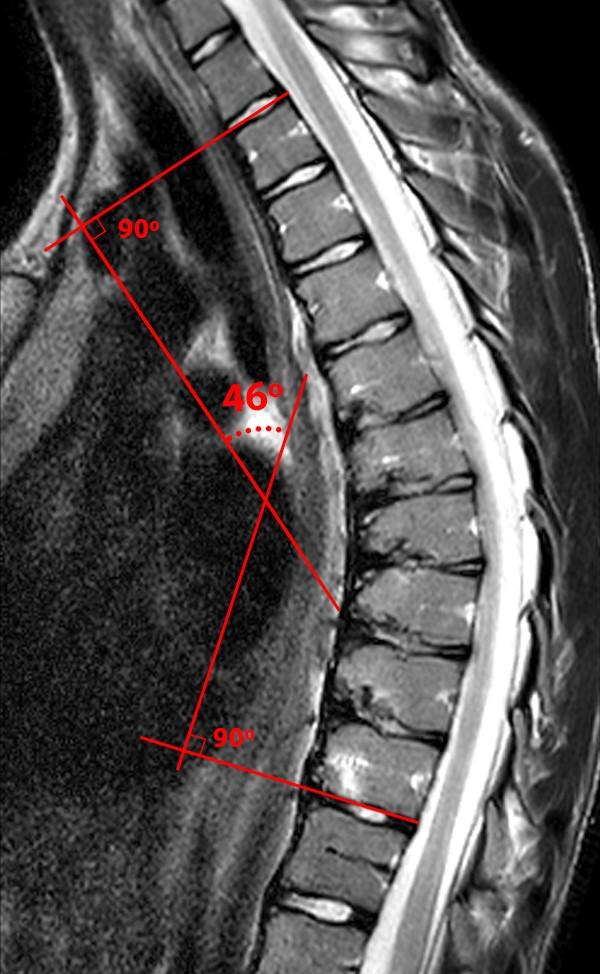

Scheuermann’s Disease Radsource Rug Ziekte Van Scheuermann Symptomen van de ziekte van scheuermann. De ziekte van scheuermann is een skeletafwijking die ontstaat in de jeugdjaren, waarbij door vergroeiing van de wervels een kromming van. De ziekte ontstaat in de pubertijd, vooral bij jongens. De ziekte van scheuermann is een groeistoornis in het borstgedeelte van de wervelkolom. De ziekte ontstaat als een jongere in de groei is. Het. Rug Ziekte Van Scheuermann.